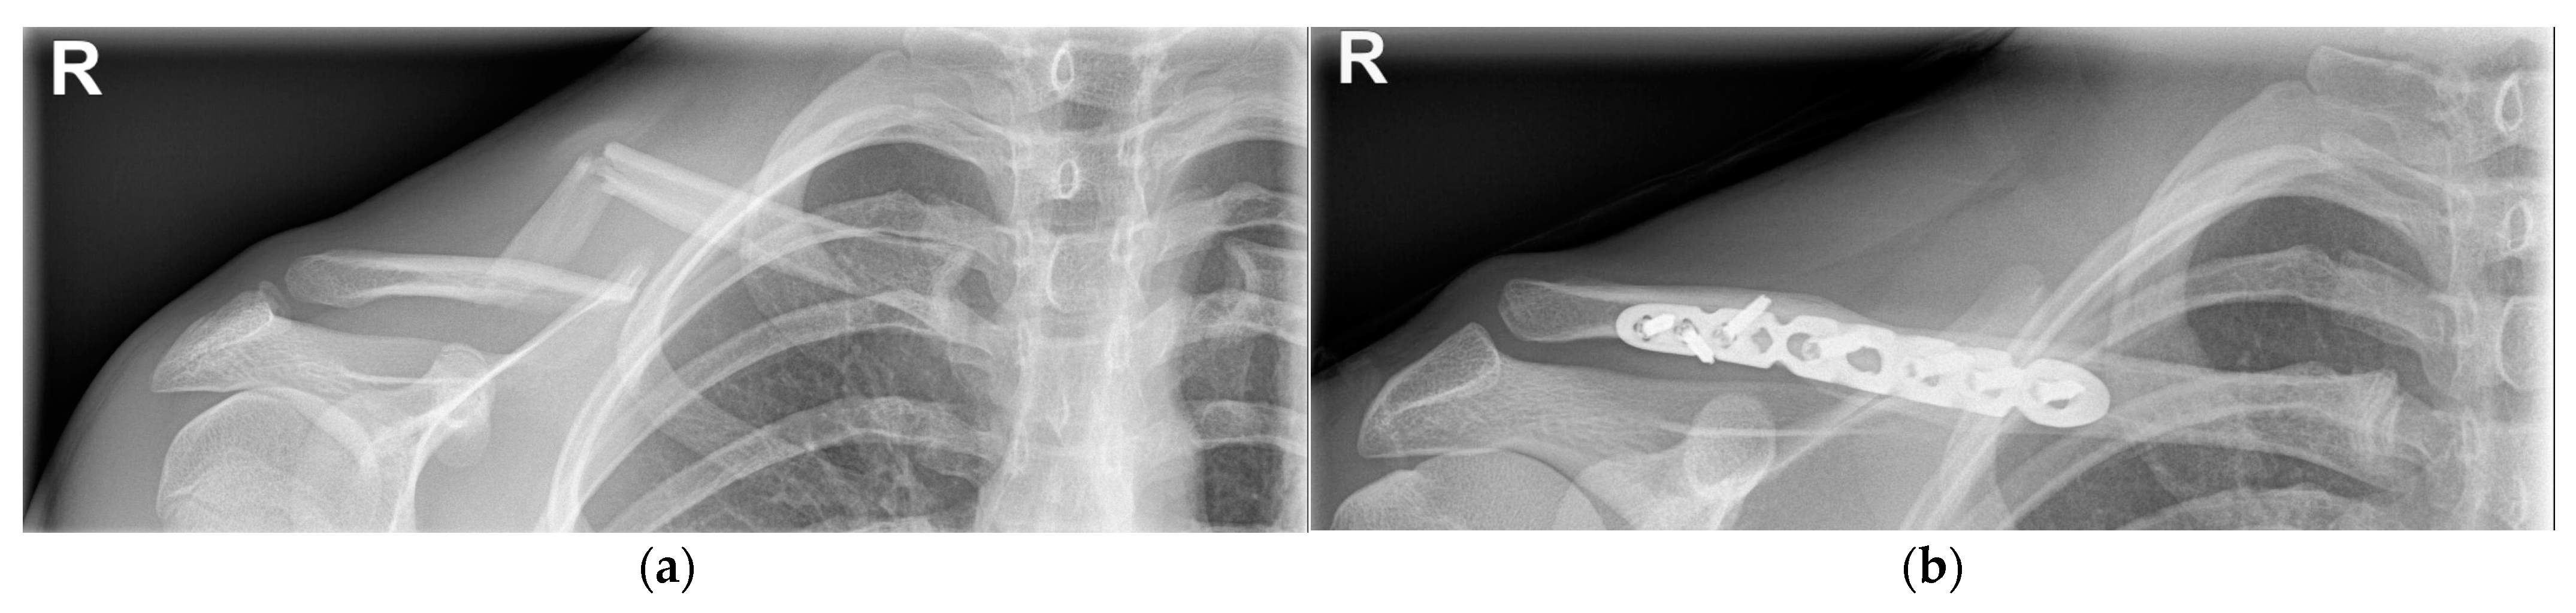

4.1.2. Operative Treatment

4.2.2. Operative Treatment